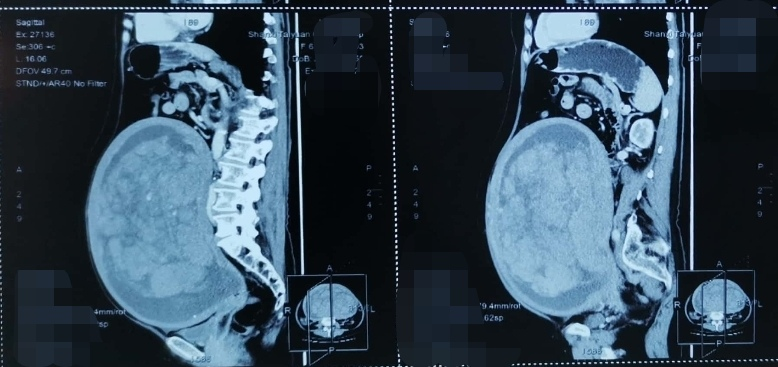

直到前幾日,李女士在家人的勸說下在當地醫院查彩超時提示:盆內巨大不均質回聲(子宮肌瘤囊性變可能,上達劍突下,右側達腋中線,左側達腋后線)。得知這一結果,她與家人都驚呆了,病情刻不容緩,巨大的子宮肌瘤對腹腔臟器的壓迫,使得她睡眠時無法仰臥,只能側臥,日常行動也“笨拙”起來。當其家人四處尋訪得知太原市中心醫院婦科在治療婦科腫瘤方面經驗豐富,而且環境溫馨,醫護人員親切熱情,于是帶著李女士前來就診。

目前,婦科手術95%以上都是微創(腹腔鏡)完成,然而李女士體內肌瘤巨大已達劍突下,不得不選擇開腹手術。考慮到李女士腫物巨大,為了把手術風險降到最低,手術醫生進行了詳細的術前討論,并制定了詳細的手術方案和應急預案,對術中可能出現的血液動力學不穩定、大出血風險高、空間局促周圍臟器損傷風險高等情況做了充分的評估及應對策略的準備。

7月29日,在麻醉手術科的保駕護航下,太原市中心醫院婦產科倪妍主任團隊為李女士成功切除了直徑36厘米、重達16斤的巨大子宮肌瘤。術中止血確切,密切關注患者生命體征,歷時1.5小時順利完成了手術,術中出血少于100ml。